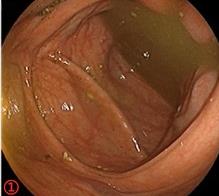

摘要:目的 探讨耳内镜下耳屏软骨-软骨膜鼓膜修补术后的短期疗效。方法 回顾性分析2019年9月-2022年8月该院收治的78例鼓膜穿孔患者的临床资料,患者均采用耳内镜下鼓膜修补术。术后随访3个月,观察鼓膜形态和穿孔愈合情况,记录内镜图像、干耳时间、术前术后听力及耳鸣情况,以及外耳道狭窄等并发症的发生率。结果 术后3个月,鼓膜穿孔愈合率为97.44%(76/78),愈合良好,平均气导听阈较术前明显改善,气骨导间距较术前明显缩小,耳鸣较术前明显改善,差异均有统计学意义(P<0.05)。干耳时间为(4.21±1.12)周。术后出现肉芽5例,再穿孔2例,真菌感染2例,术腔感染、耳屏感染、外耳道狭窄和切口瘢痕各1例,所有患者术后均未发生面神经麻痹和感音神经性聋等严重并发症。结论 耳内镜下耳屏软骨-软骨膜鼓膜修补术是一种安全、有效的手术方法。根据术后愈合规律、内镜下鼓膜和外耳道形态特征,可为鼓膜修补术后正常中耳转归和并发症的诊疗,提供临床参考。